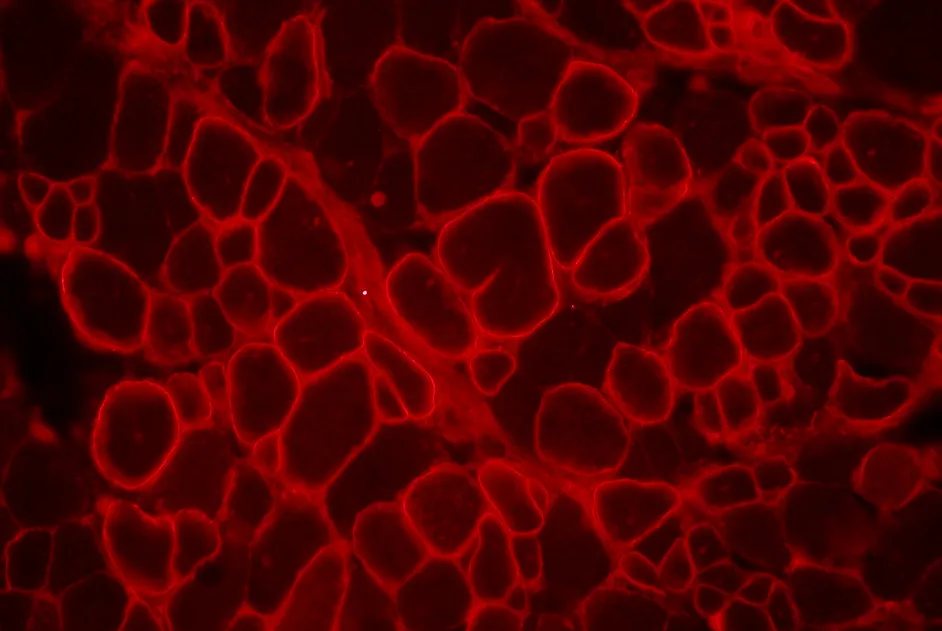

Dans le but de développer un meilleur modèle animal, une équipe européenne soutenue par l’AFM-Téléthon a mis au point une souris modèle appelée Rag2-Il2rb-Dmd-. Ces souris modèles sont dystrophiques mais sans fibre révertante et totalement immunodéficientes (absence de défense immunitaire) ce qui permet l’étude d’une transplantation de myoblastes humain à long terme (sans rejet de la greffe par le système immunitaire) sans rejet immunologique.